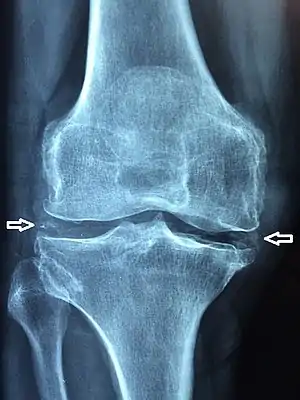

The disease is defined by the presence of joint inflammation and CPPD crystals within the joint. The crystals are usually detected by imaging or joint fluid analysis. X-ray, CT, or other imaging usually shows accumulation of calcium within the joint cartilage, known as chondrocalcinosis. There can also be findings of osteoarthritis.[12][9] The white blood cell count is often raised.[9]

Medical imaging, consisting of x-ray, CT, MRI, or ultrasound may detect chondrocalcinosis within the affected joint, indicating a substantial amount of calcium crystal deposition within the cartilage or ligaments.[13] Ultrasound is a reliable method to diagnose CPPD.[14] Using ultrasound, chondrocalcinosis may be depicted as echogenic foci with no acoustic shadow within the hyaline cartilage[15] or fibrocartilage.[14] By x-ray, CPPD can appear similar to other diseases such as ankylosing spondylitis and gout.[13][9]

X-ray of a knee with chondrocalcinosis.